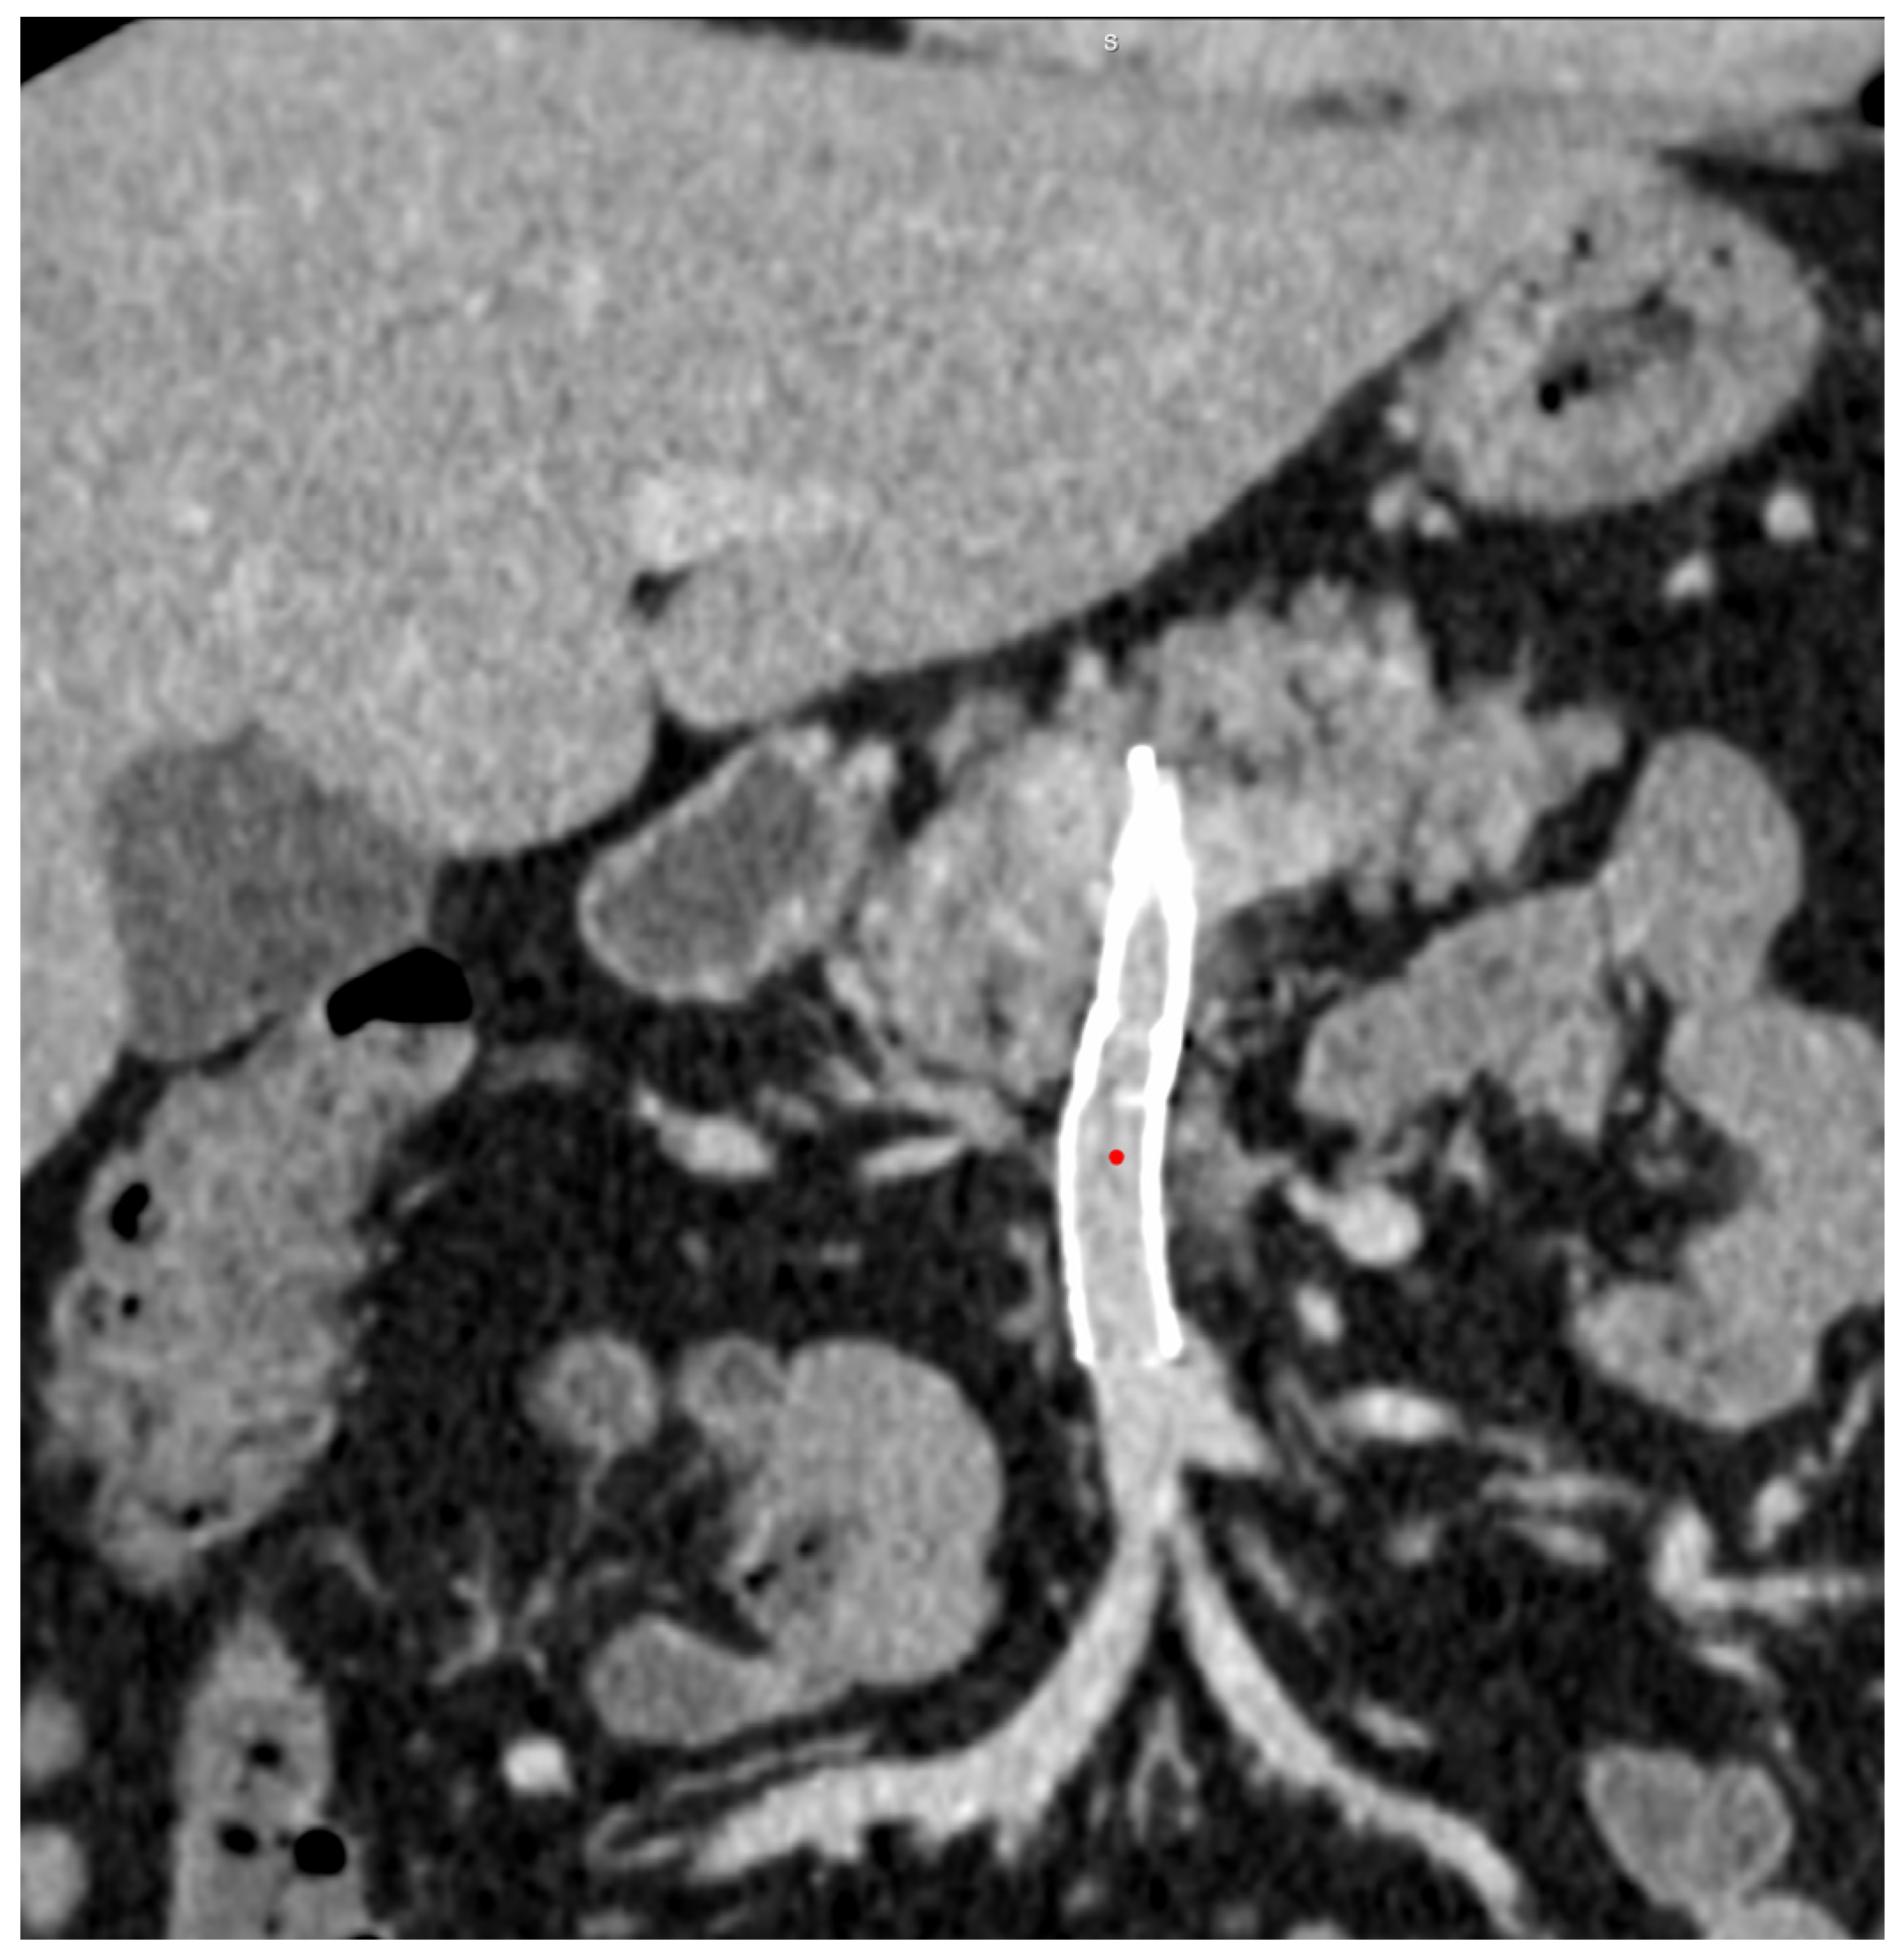

Endovascular Stenting for Idiopathic Stenosis of the Superior Mesenteric Vein: A Case Report

2. Case Report